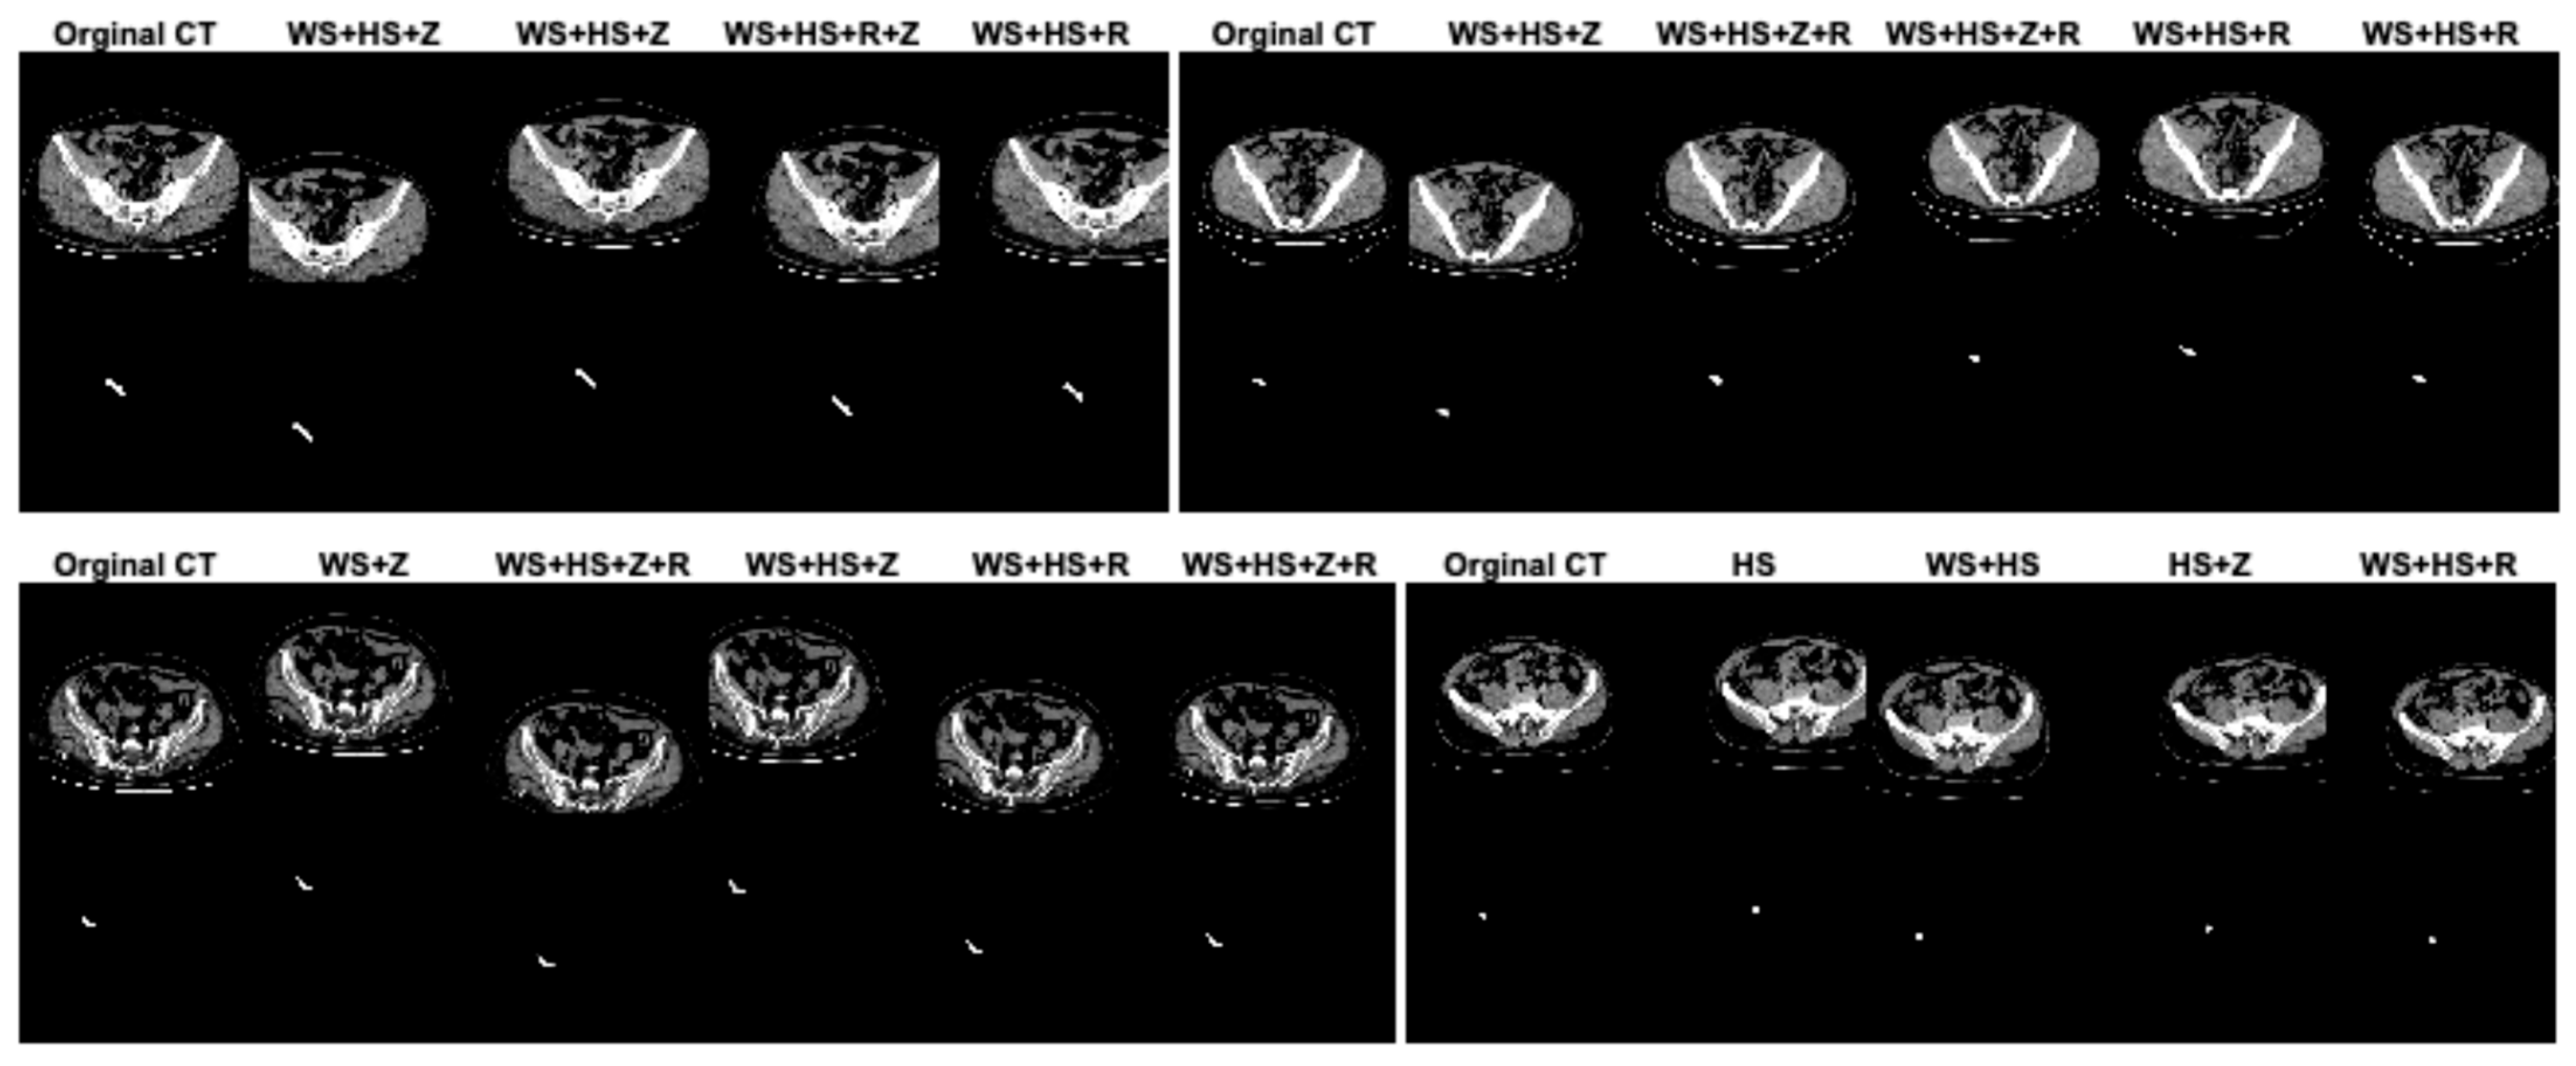

In this study, data augmentation was performed to address several key challenges in training deep learning models for appendix segmentation in CT scans. Data augmentation was applied to artificially increase the size and variability of the prepared dataset. This helps to avoid overfitting [], where the model memorizes the training data rather than learning generalizable features. In addition, the CT scans in the dataset can vary significantly between patients in terms of anatomical differences, scan quality, patient position and image noise. The data augmentation enables the proposed U-Net deep learning architecture to learn more robust and discriminative features. This improves the model’s ability to generalize to unseen data by simulating variations in real CT scans. In this study, in the original dataset prepared for appendix segmentation, the number of slices in the training set was increased from 1199 to 2399, the number of CT slices in the test set was increased from 221 to 441, and the total number of slices was increased from 1420 to 2840 using data augmentation strategies. The data augmentation procedures used to increase the size of the dataset were width_shift_range = 0.2 (WS), height_shift_range = 0.2 (HS), rotation_range = 2 (R) and zoom_range = 0.05 (Z). The data augmentation procedures for the dataset were randomly generated on both training and test sets separately or together. Figure 4 shows the effect of the data augmentation procedures on some CT scans and GT masks in the dataset.

Figure 4.

The effect of the data augmentation procedures on some CT scans and GT masks in the dataset.